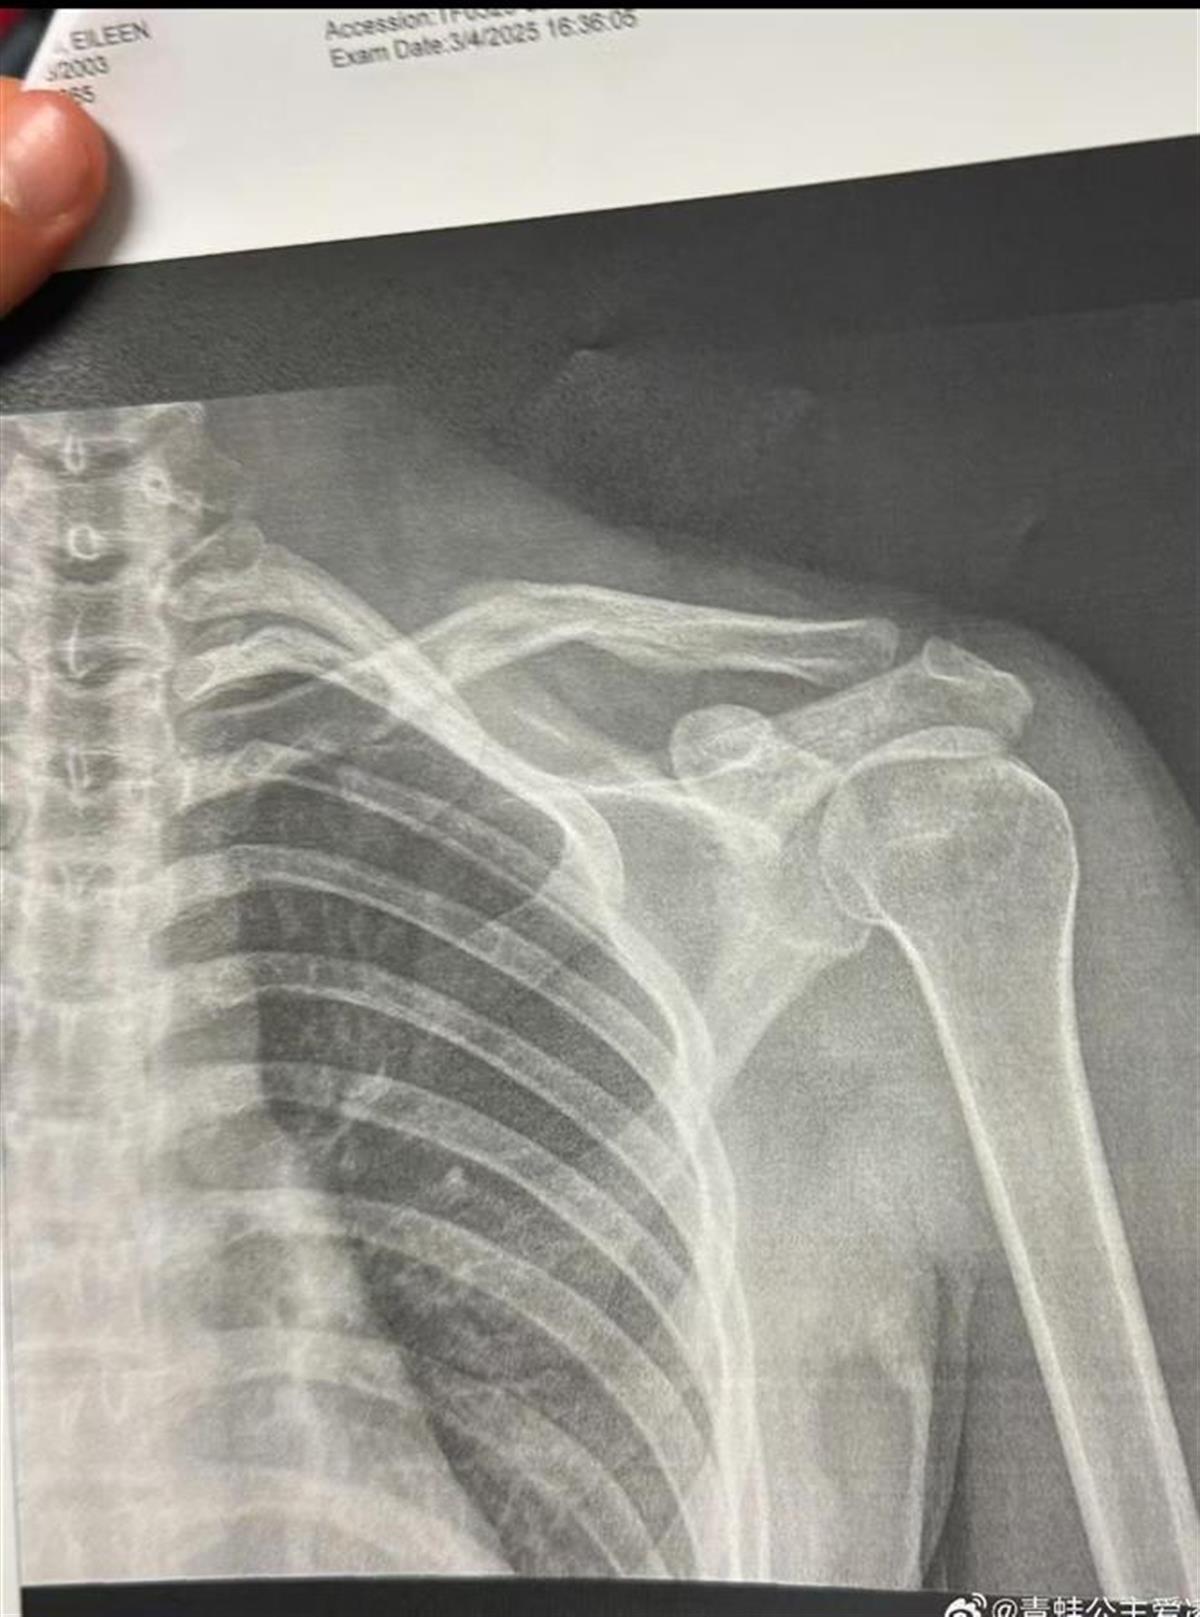

3月9日,中国自由式滑雪运动员谷爱凌在社交媒体晒出肩部骨折的X光照片,并配上一个心碎的表情,随后相关话题登上热搜。

X光照片上显示的时间为2025年3月4日,是旧伤还是新伤,目前尚不清楚。不过,这已经不是谷爱凌第一次受伤,实际上,今年1月以来,她已多次受伤。